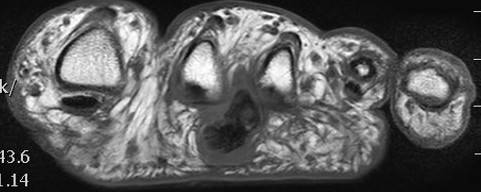

MRI

Focal oval shaped lesions within the plantar fascia